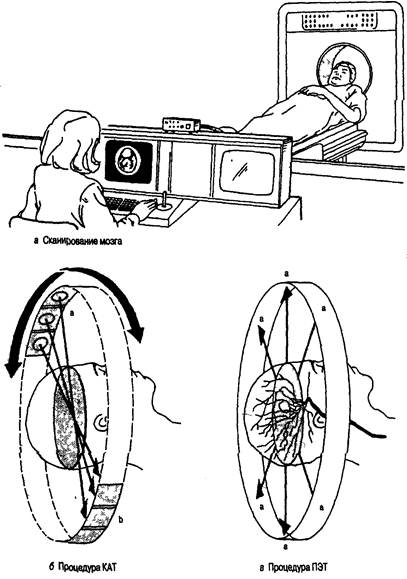

Начиная с 1-го и вплоть до 6-го издания «Когнитивной психологии» общая структура статей мало изменилась, но значительно изменилось их содержание. В первых изданиях мы лишь вскользь упоминали о теме, которая сейчас называется нейропознанием (термин начал широко применяться только в начале 1980-х годов). Сейчас же важная роль нейропознания во всех сферах когнитивной психологии (так же, как и в остальных сферах) очевидна, и дошло до того, что этот раздел когнитивной науки начал вытеснять из учебников другие, более традиционные области. Значительные успехи в нейропознании (не только в методах, но и в способах получения данных и их интерпретации) в полной мерой отражены в настоящем издании учебника, хотя мы не забывали и о том, что когнитивная психология — это прежде всего наука о человеческом разуме: мыслях, умозаключениях, языке, памяти и роли сенсорных стимулов. Эти и другие проблемы познания иллюстрирует, объясняет и разъясняет нейропознание (более чем на одном уровне). Ввиду того что познание изучается психологией, я сохранил описание многих традиционных исследований, которые выдержали испытание временем и эмпирическую проверку, и добавил новые интересные материалы там, где это было необходимо. Всегда существует большой соблазн заменить старые концепции на новые, но эта замена оправданна лишь в тех случаях, когда более современные труды отображают новый аспект проблемы. В большинстве случаев старые исследования безупречно ясны, поэтому я оставил их без изменений. Кроме того, в связи с ростом интереса к психологическим аспектам когнитивной психологии в 6-м издании упомянуто множество нейрокогнитивных исследований, которые были включены в издание как новые доказательства когнитивных теорий. Создание первого варианта «Когнитивной психологии» более 20 лет тому назад было особенно сложной задачей, так как я не имел никакого примера для подражания, кроме изданной в 1967 году и ставшей классической книги Ульрика Найссера с таким же названием и сотни статей и материалов симпозиумов, в беспорядке разбросанных у меня в офисе и дома. Мне действительно повезло, когда в 1974 году я оказался на лекциях Эда Смита о познании в Стэнфордском университете (курс лекций, который позже читал я). Его организация материала отражена (хотя с некоторыми изменениями) в данной книге, так же как и во многих других учебниках о познании, и мне кажется, что Эд Смит, который был принят в Национальную академию наук, оказал большое влияние на то, как преподается когнитивная психология в Соединенных Штатах и во всем мире. Существует несколько дюжин учебников по когнитивной психологии и еще много других книг, в которых обсуждаются такие темы, как познание и юриспруденция, познание и психотерапия, познание и общество, познание и образование и т. д. Начиная с периода «когнитивной революции» сфера влияния занимающихся этой темой специалистов расширилась намного больше, чем я мог вообразить десятилетия назад. Однако, на мой взгляд, главные темы, сформировавшие эту дисциплину в то время, все еще актуальны, хотя за прошлые годы акцент сместился, — таков динамический характер жизнеспособных наук. Мне нравилось писать эту книгу, и, могу нескромно добавить, я даже с удовольствием перечитывал ее время от времени; теперь же, когда я ее заканчиваю, пришло время оглянуться назад с некоторой ностальгией. Когда я начал работать над 1-м изданием, у меня были лишь чистый лист линованной бумаги, обещавшая стать обшарпанной авторучка и сотни статей, журналов и книг по восприятию, памяти и мышлению в качестве материала для работы. Теперь я работаю, используя компьютер, который сам проверяет правописание и синтаксис (иногда), множество книг, подобных моей, и столько новых данных, сколько не сможет переварить ни один человек. Я надеюсь, что мои книги внесли важный вклад в психологию и науку в целом. Для меня это было путешествие, от которого я не мог отказаться. В этом, 6-м, издании я пытался сохранить лучшие черты предыдущих пяти изданий, добавив важные новые материалы и несколько сместив акцент книги, желая отразить последние изменения. В частности, я сохранил всесторонний характер книги. Есть опасность написать всеобъемлющий учебник, читая который студенты могут увязнуть в огромном количестве материала, содержащегося в одном курсе. Могу дать вам совет: не нужно изучать всю книгу за один семестр. Немного позже я продолжу эту тему. В течение последнего десятилетия когнитивная психология претерпевает существенные изменения и бурно развивается, нам стало намного труднее корректно раскрывать все области познания. Я выделил основные исследования и идеи и устранил некоторые из наиболее специальных аспектов когнитивной науки. Несомненно, специализированные книги, написанные с особой точки зрения, необходимы, но я полагаю, что многие будут приветствовать появление всеобъемлющей книги по когнитивной психологии, — задача, которую пытались решить лишь несколько авторов. Тем из вас, кто уже знаком с «Когнитивной психологии», будет приятно обнаружить, что в книге представлены противоречивые данные, сопровождаемые некоторыми примечаниями. Такие резюме впервые использовались в 3-м издании с учетом пожеланий многих читателей. Я также вел активные лабораторные исследования, в которых вместе со своими студентами проверял кое-какие из идей, изложенных в этой книге. Иногда мы будем обращаться к данной работе, чтобы разъяснить конкретные принципы и показать читателю, что когнитивная психология — активная, развивающаяся наука. Я надеюсь, что такие исследования будут стимулировать вас продолжить поиск более полных ответов на поставленные в книге вопросы. Как и в предыдущих изданиях, большинство глав начинается с краткого исторического обзора соответствующей темы; однако в некоторых главах этот обзор был сокращен, чтобы освободить место для текущей информации. Так как когнитивная психология как наука быстро развивается, я полагаю, что для читателей важно знать кое-что об истории темы, чтобы они могли понять новую информацию в контексте прошлых событий. В пятый раз перерабатывать столь нежно любимую книгу — сладостно-горький опыт. С одной стороны, действительно приятно включить в нее новые исследования, которые отвечают на некоторые из вопросов, поставленных в предыдущих изданиях; с другой — смотреть на пол, заваленный удаленными страницами, параграфами и примерами тщательно обработанного материала, для того, кому тяжело сократить даже одно слово, — все равно что видеть, как умирает часть твоей интеллектуальной жизни. Мне особенно не хотелось сокращать часть исторического материала по исследованиям памяти, но требовалось место для рассказа о более интересных открытиях. Кроме добавления новых ссылок в большинстве глав и удаления некоторых устарелых исследований в этом издании подчеркнуты следующие моменты: * Каждая глава начинается с предварительных вопросов. Мы знаем, что усваивать важную информацию легче, если студент имеет представление о том, что именно он, как ожидается, будет изучать. Несколько наводящих вопросов в начале главы определяют направление внимания студента при дальнейшем чтении; в некоторых случаях вопросы сформулированы так, чтобы вызвать особый интерес читателя. Вообще, это издание более удобно в использовании и в то же время стимулирует интеллектуальную активность. * Каждая глава была обновлена, а несколько глав были значительно переделаны, часто в ответ на просьбы читателей. Это касается глав, посвященных восприятию и вниманию, сознанию и когнитивному развитию. * Книга существенно дополнена новой информацией по физиологии и смежным темам, включая недавно полученные результаты по технологиям нейрокогнитивного отображения. Включение этих тем — ответ на быстро изменяющийся характер когнитивной психологии и важные новые открытия в области науки о мозге и нейропознании. * В данном издании мы объединили материал некоторых глав; в особенности это касается самостоятельных в прошлых изданиях глав, посвященных восприятию и вниманию, которые были объединены в одну главу. * Организация глав и разделов соответствует последовательности обработки информации, которая начинается с восприятия сигналов сенсорной/мозговой системой и продолжается в рамках процессов более высокого порядка, таких как память, язык и мышление. Именно этой последовательности легче следовать студентам и преподавателям, хотя когнитивная модель обработки информации {Information Processing — INFOPRO) — не единственная модель, с которой могут ознакомиться студенты, читая эту книгу. По моему мнению, познание имеет сложный характер и все его части работают вместе более или менее одновременно. Хотя люди не испытывают трудностей в использовании модели последовательной обработки, следует отметить, что память без восприятия похожа на красивую живопись без краски. * В большинство глав включен раздел под названием «Критические размышления», в котором я призываю читателя анализировать или рассматривать ту или иную тему. Я обнаружил, что этот прием, как и другие, которые вы могли бы придумать сами, является хорошим средством стимулирования обсуждения в группе. Студенты склонны более глубоко обдумывать проблемы и лучше усваивать информацию, когда обсуждают тему с другими студентами. Дискуссия в группе также дает студентам возможность упражнять и улучшать их аналитические навыки. * Добавлен новый иллюстративный материал, который является одновременно живым и поучительным. При написании всеобъемлющей книги по когнитивной психологии я пытался сделать так, чтобы моя работа была привлекательна для многих преподавателей, предпочитающих выбирать свои любимые темы для семестрового курса лекций. Можно изложить материал всех шестнадцати глав в одном курсе, но большинство преподавателей говорили мне, что они выбирают лишь некоторые главы. (В свой собственный курс лекций я включаю все, кроме одной или двух глав, хотя один мой деятельный аспирант изложил всю книгу за одну пятинедельную летнюю сессию !) Я написал этот учебник так, чтобы некоторые главы могли быть опущены без ущерба для целостности книги. Вот несколько предлагаемых моделей: 1. Краткое общее введение в познание — главы 1, 3, 4, 6-8, 11, 13, 15 и 16. 2. Нейрокогнитивная система — главы 1-5, 7-10, 12, 15 и 16. 3. Прикладной подход — главы 1, 3-11, 13-16. 4. Мышление/с акцентом на решение проблем — главы 1, 4-11, 14-16. 5. Память — главы 1-3, 6-15. 6. Когнитивное развитие — главы 1-4, 6-16. Эти модели — лишь общие предложения, к которым можно добавить главы по вашему вкусу и/или специализации. В написание этой книги внесли вклад многие люди, и я с удовольствием отдам им дань уважения. Многие из вас, преданных читателей, в течение этих лет лично или в письмах выражали свое мнение о книге. Я глубоко ценю вашу верность этой книге, и ваши замечания были для меня очень важны. Кроме того, я узнавал мнения (в форме писем и иным способом) студентов — самой важной группы читателей, которым адресована эта книга. Многие исследователи информировали меня о своих последних открытиях, и я особенно обязан им. Многие из вас присылали мне копии рукописей и опубликованных работ из источников, которые иначе было бы фактически невозможно найти. Я выражаю признательность рецензентам прежних изданий. Я благодарю Кристи Ланда за помощь в подготовке рукописи. Данное издание было в известной мере улучшено обзорами, присланными Томом Бузи (Университет штата Индиана), Уильямом С. Кассэлем (Университет Нового Орлеана), Линдой Д. Кросняк (Университет Джорджа Мейсона), Дарлин Демари-Дреблоу (колледж Маскингам), Дугом Имоном (Университет Висконсина в Уайтуотере), Полом Фусом (Университет Северной Каролины в Шарлотте), Полом Хосе (Университет Лойолы в Чикаго), Кристи А. Нильсон (Университет Маркетт), Грэгом Робинсоном-Риглером (Университет св. Фомы), Барбарой А. Спеллман (Университет Вирджинии), Лаурой А. Томпсон (Университет штата Нью-Мексико). Наконец, я благодарю моего редактора Кэролин Меррилл, моих студентов и коллег, которые обеспечивали поддержку и помощь, а также вдохновляли меня. Я также благодарю Габриэля А. Флореса за его восхитительные иллюстрации. Р. Л. С.ГЛАВА 1. Введение в когнитивную психологию